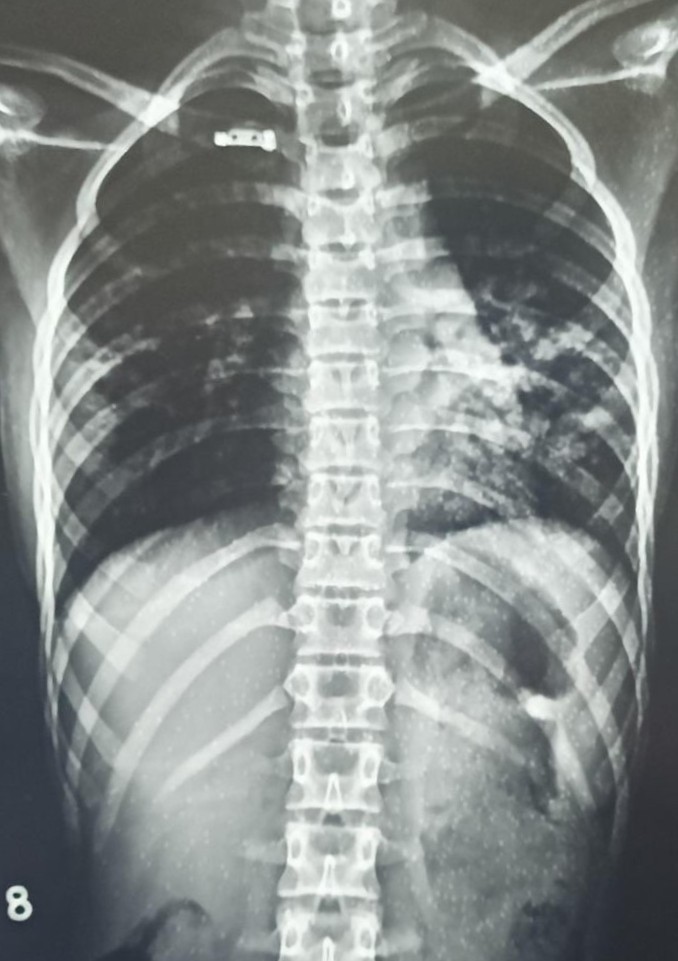

| 4404 | IGGMC, Nagpur, Nagpur | P2 | 29-68 | Gauri Rathod | Consent taken on Paper | 12 Yrs. |

Provisional Diag : Lower Respiratory Tract Infection

Final Diag : LEFT LOWER ZONE INFILTRATIONS |

Non-TB Case (Confirmed) | Left Mid Zone Radiopacity/ clothing Artifact | Abnormality visible on x-ray |